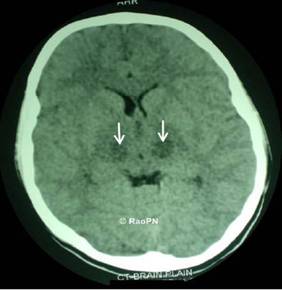

Nếu chỉ có một mẫu huyết thanh, thì hiệu giá kháng thể cao hơn 1/320 mới được xem là dương tính. Hiện nay phản ứng thường được dùng là phản ứng MAC ELISA. Phản ứng MAC ELISA: (IgM antibody capture enzyme linked immunosorbent assay): tìm kháng thể IgM, là kháng thể nói lên một nhiễm trùng mới mắc. Phản ứng này giữ vai trò quan trọng trong chẩn đoán và nghiên cứu dịch tễ học các bệnh nhiễm trùng vì kỹ thuật đơn giản và ít tốn kém. Nói chung các phản ứng huyết thanh đều có độ nhạy cao, nhưng độ đặc hiệu lại kém vì có phản ứng chéo với các giòng Flavivirus, nhất là tại những nơi có bệnh sốt Dengue, sốt xuất huyết hoặc Flavi khác lưu hành. Ngoài biện pháp phân lập virút trên các bệnh phẩm, hiện nay kỹ thuật MAC ELISA được sử dụng tìm IgM đặc hiệu trong dịch não tủy để xác định bệnh viêm não Nhật Bản trên các bệnh phẩm, hiện nay kỹ thuật MAC ELISA được sử dụng tìm IgM đặc hiệu trong dịch não tủy để xác định bệnh viêm não Nhật Bản. Phản ứng này có độ nhạy 75% trong giai đoạn cấp, trên 95% trong giai đoạn đang hồi phục, với độ chính xác > 95%. Kỹ thuật khuyếch đại gien (Polymerase Chain Reaction - PCR) là phương pháp nhân RNA của virút trong các bệnh phẩm như dịch não tủy, máu, mẫu não và tủy sống. Có thể là công cụ chẩn đoán nhiều hứa hẹn trong tương lai. Trong giai đoạn cấp thường thấy điện não đồ hoạt động sóng nhọn, gai chậm hoặc nhiều gai xen lẫn với những hoạt động chậm. Trong giai đoạn bán cấp hầu hết các trường hợp đều có sóng chậm lan tỏa ở cả hai bán cầu và có xu hướng ưu thế ở một bên. | Hình ảnh chụp CT scan não bệnh nhân viêm não Nhật Bản |

Chụp cắt lớp điện toán (CT scan - computerized tomography), cộng hưởng từ (MRI - magnetic resonnance imaging). Kết quả 50% chụp cắt lớp điện toán ở bệnh VNNB có hình ảnh giảm tỷ trọng ở một hay nhiều chỗ ở những vùng đồi thị, nhân xám nền sọ, não giữa, cầu não, hành tủy. Hình ảnh cộng hưởng từ thường rõ và nhạy hơn, cho thấy có tổn thương lan tỏa, ở hai bán cầu não, tiểu não, và có hình ảnh của xuất huyết tại đồi thị.